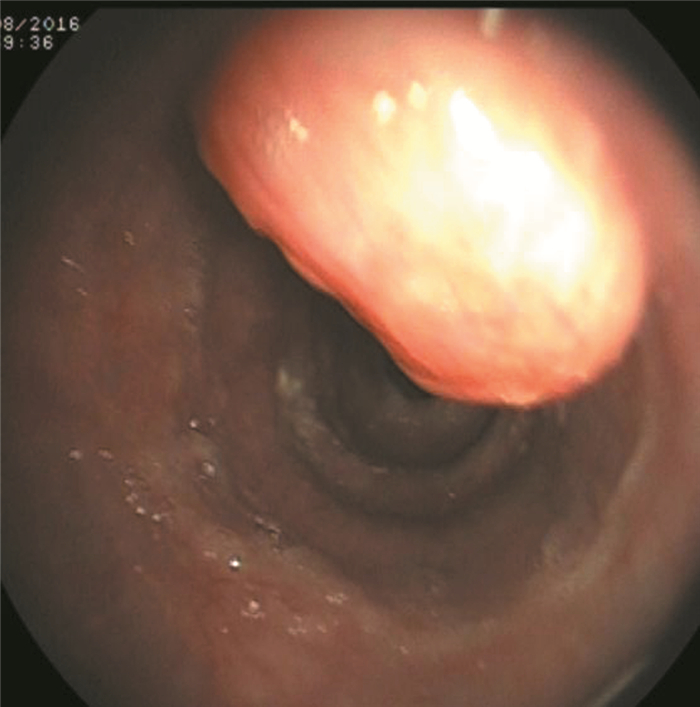

血常规:中性粒细胞百分比84.1%、血小板49×109/L,余正常。尿常规、粪常规、甲胎蛋白、癌胚抗原、糖类抗原199、甲状腺功能、CRP、血清降钙素原正常。乙型病毒性肝炎 (乙肝) 三对、丙型病毒性肝炎 (丙肝) 病毒抗体、抗HIV、血幽门螺杆菌抗体、梅毒特异性抗体、抗核抗体均阴性。A型血、Rh (+)。肝功能:总胆红素44.3 μmol/L、直接胆红素12.1 μmol/L、间接胆红素32.2 μmol/L、ALT 46 U/L、AST 63 U/L、碱性磷酸酶179 U/L、γ-谷氨酰转移酶103 U/L。电解质:钾3.4 mmol/L。凝血常规:凝血酶原时间16.3 s、国际标准化比率1.34、部分凝血活酶时间55.2 s。X线胸片、胸部CT示双肺未见明显异常。上腹部CT示肝硬化、脾大、门脉高压、腹水、胆囊结石并胆囊炎。腹部彩超示肝硬化、脾大、腹腔积液、门静脉内径增宽、胆囊继发改变、胆囊多发结石。胃镜示食管静脉曲张 (轻度)、食管肿物 (表面光滑,未见糜烂及溃疡形成),见图 1。入院诊断“肝硬化失代偿期 (酒精性)、门脉高压症、脾功能亢进症”基本明确,但此次胃镜下发现食管中上段肿物,性质尚不明确,行超声胃镜示食管固有肌层肿物 (考虑间质瘤),见图 2。病理检查结果示 (食管) 小细胞恶性肿瘤、结合免疫组织化学 (组化) 符合小细胞癌。免疫组化结果示CgA (+),CK5/6(-),CKpan (+),K1-67(+50%~75%),LCA (-),NSE (+),P63(-),Syn (+),TTF-1(+),见图 3

图 2 PESCC患者超声胃镜图

本例患者为65岁老年男性,主要临床症状为腹胀、腹水、纳差、乏力等肝硬化失代偿期表现,诊断为肝硬化失代偿期 (酒精性)5年,此次患者起病隐匿,临床症状不典型,入院前缺乏吞咽梗阻感或胸骨后不适等食管肿瘤特异性表现,易漏诊。本例患者特别之处在于食管肿物表面光滑,未见糜烂及溃疡形成,易误诊为平滑肌瘤,延误病情的诊治。本例结合胃镜、病理及免疫组化结果明确为肝硬化失代偿期合并PESCC,且病灶位于食管中上段,临床上极为罕见,与文献报道不一致。本例患者未进行食管静脉套扎及硬化治疗,原因可能与酒精、营养不良及反流有关,有待进一步研究证实。